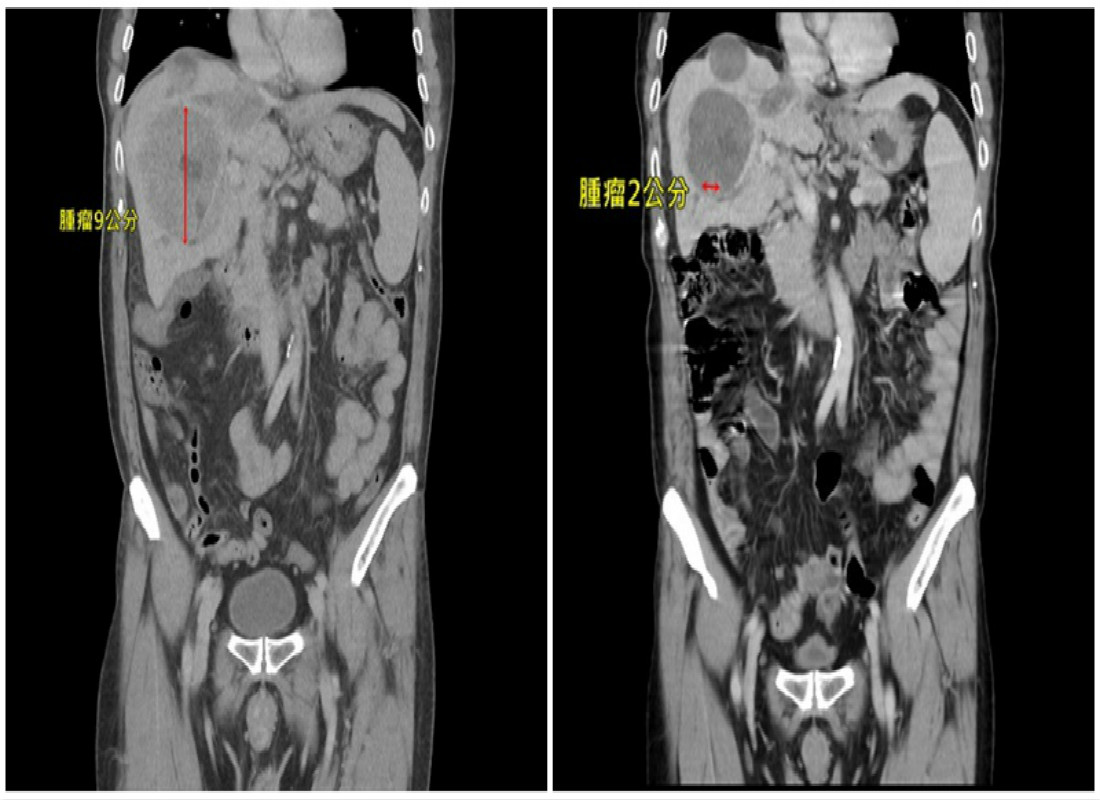

另一名65歲許伯伯患有B肝卻疏於追蹤,近日因感到容易喘,診斷時發現腫瘤已侵犯兩肝,肝門靜脈、下腔靜脈快塞到心臟,已是肝癌第三期,預估存活率不到1年,經光子刀合併四次免疫治療,肝內腫瘤及血管栓塞接近全消除,治療過程也無不適,甚至感覺體力越來越好,也可繼續手邊的工作。